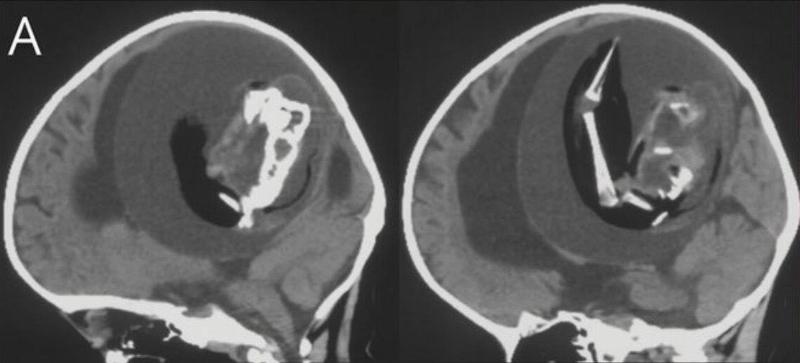

This rarely-seen, frightening medical anomaly was recently discovered in a one-year-old girl in China, shocking neurologists worldwide.

It all began when the girl's parents brought her to the hospital for some scans as she was sporting an enlarged head and was struggling with her motor skills. They assumed the two issues were connected and were greatly concerned for their baby's safety.

Doctors performed CT scans on the young girl's skull and were shocked to discover a four-inch parasitic fetus within her brain.

This condition, wherein an underdeveloped twin's fetus fuses to the host twin and continues growing within them, is called fetus-in-fetu.

Once the CT scans revealed the existence of her twin that was pressing against her brain, doctors knew they had to remove it immediately. By the time they were able to extract it, it had been growing inside the girl's skull for months, long enough for it to develop bones, organs, and limbs.

The entire case was studied heavily, so much so that it was published as a story in the American Academy of Neurology's journal, Neurology.

Dr. Zongze Li, a neurologist at Huashan Hospital who treated the girl, said, "The intracranial fetus-in-fetu is proposed to arise from unseparated blastocysts. The conjoined parts develop into the forebrain of the host fetus and envelop the other embryo during neural plate folding."

They reported that the parasitic twin was able to survive for so long as it shared a blood supply with the healthy twin, and though the extraction was a success, there's no knowing if the healthy twin will suffer any long-term damage caused by the parasite.